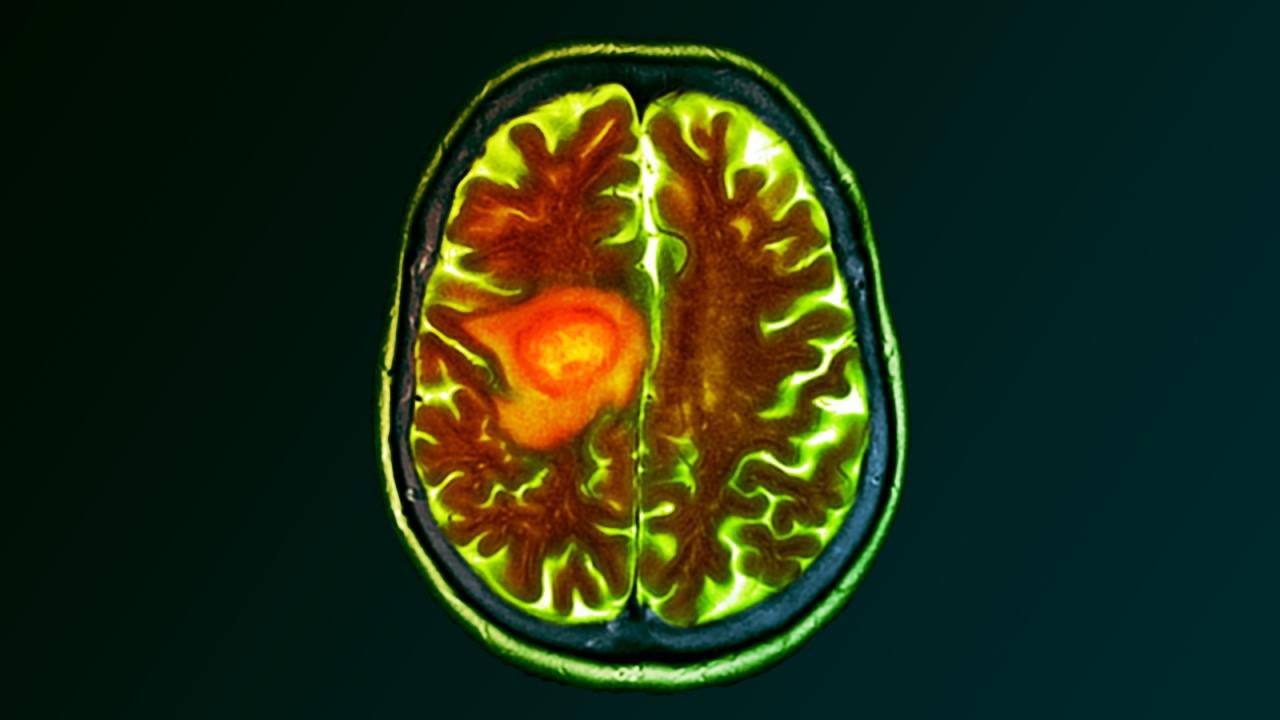

Az anyagcsere átállítása: a rák Achilles-sarka

A Michigani Egyetem kutatói kimutatták, hogy a glioblasztóma sejtjei teljesen átalakítják saját energiaellátó rendszereiket. Míg az egészséges agysejtek a cukorból nemcsak üzemanyagot, hanem szerin nevű aminosavat is előállítanak – ami elengedhetetlen az idegi ingerületátvitelhez –, a tumorsejtek ezt a folyamatot elvetik. Ezek a daganatos sejtek a cukrot szinte kizárólag nukleotidok – vagyis a DNS építőelemei – előállítására fordítják, így biztosítják saját osztódásukat és javítják önmagukat, amikor például a sugárkezelés károsítja a DNS-üket.